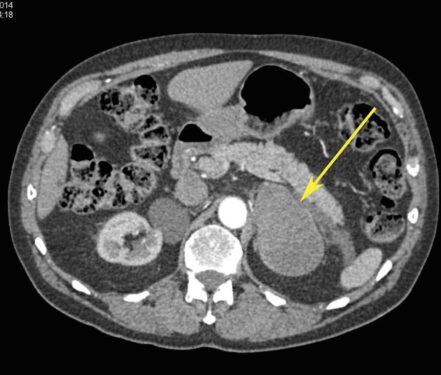

TC DE GLANDULAS SUPRARRENALES.

La hemorragia suprarrenal es una entidad infrecuente que puede ser uní o bilateral.

Cuando es unilateral suele ser clínicamente silente y en la mayor parte de los casos se diagnostica de forma incidental.

Las causas de hemorragia suprarrenal se dividen en traumáticas (la mayoría unilaterales y derechas) y espontaneas, agudas y crónicas.